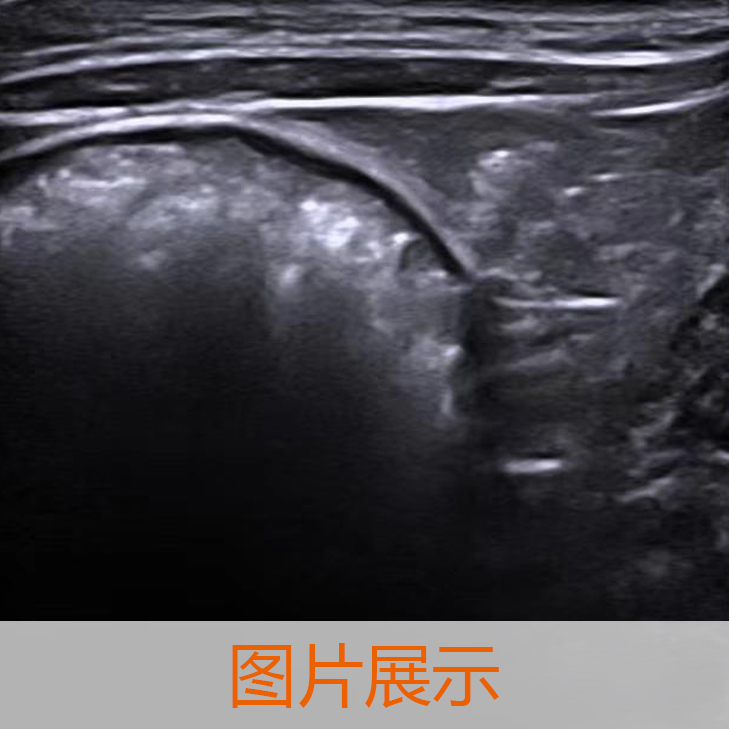

高(gāo)端獸用(yòng)彩色多(duō)普勒超聲診斷系統

型号:ROYO P70 VET

簡述:ROYO P70 VET 獸用(yòng)超聲診斷系統由 Hi 平台提供支持,它不(bù)但(dàn)有(yǒu)出色的(de)圖像性能(néng),還(hái)有(yǒu)專業(yè)的(de)獸醫(yī)軟件(jiàn)及專業(yè)的(de)測量工(gōng)具包。它也(yě)可(kě)以緊湊地(dì)折疊到(dào)最小(xiǎo)高(gāo)度小(xiǎo)于 80 厘米。此外(wài),ROYO P70 vet 結合了(le)時(shí)尚的(de)外(wài)觀、符合人(rén)體(tǐ)工(gōng)程學的(de)設計(jì)、全面的(de)臨床功能(néng)和(hé)專用(yòng)的(de)獸醫(yī)智能(néng)工(gōng)作(zuò)流程。這(zhè)種完美(měi)的(de)結合帶來(lái)了(le)為(wèi)獸醫(yī)量身(shēn)定制(zhì)的(de)新一(yī)代超聲系統。